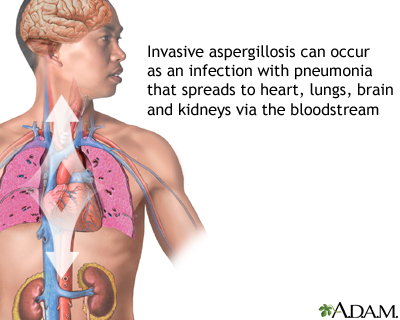

Pulmonary aspergilloma is a mass caused by an infection by the fungus aspergillus. It usually grows in preexisting lung cavities. The infection can also appear in the brain, kidney, or other organs.

Complications of pulmonary aspergilloma may include:

- Spread of the infection